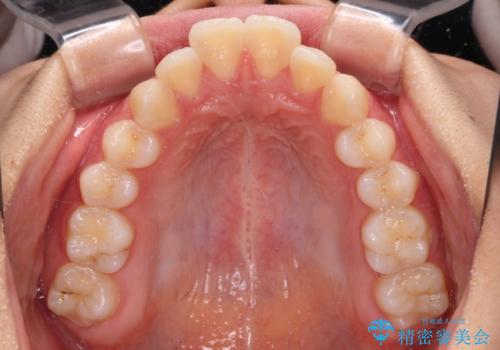

舌の突出癖などにより、上下前歯の間に指が入るくらい隙間のできる状態でした。

下顎は叢生があったため、上下左右の第一小臼歯4本を抜歯し、更には口元の突出感を大きく改善させるために、上顎臼歯を後方に移動させるための補助装置をしようし、ワイヤー装置にて矯正治療を行うこととしました。

舌の突出癖は十分に改善されたとは言えない状態でしたので、今後の後戻り防止対策として、経過観察中も舌のトレーニング指導を行っていくこととなります。